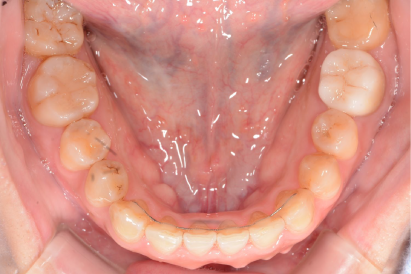

術後

年代、性別

10代、女性

職業

学生

主訴

歯並び相談

部位

抜歯を併用してのインビザラインによる全顎矯正

治療期間

2年

矯正費用

95万円

施術説明

前歯が突出感と、下歯がガチャガチャしていることを改善したいということでした。マウスピース矯正は抜歯を伴う矯正は難しいという意見もありますが、適切に診査・診断を行い対応すれば問題ありません。本症例では、上下2本ずつ合計4本の抜歯を行い、スペースを作ることで、上記の問題を矯正で改善しました。非常に綺麗な歯並びになり、非常に喜んでもらえました。

副作用・リスク

なし